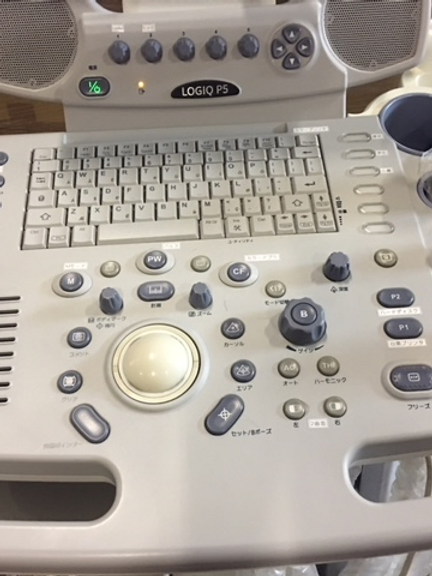

Introduction: Experience cutting-edge imaging technology at an affordable price with the LOGIQ P5 Ultrasound Scanner. Compact, ergonomic, and packed with high-end features, this ultrasound device redefines diagnostic excellence without breaking the bank.

- Compact and ergonomic design for enhanced usability